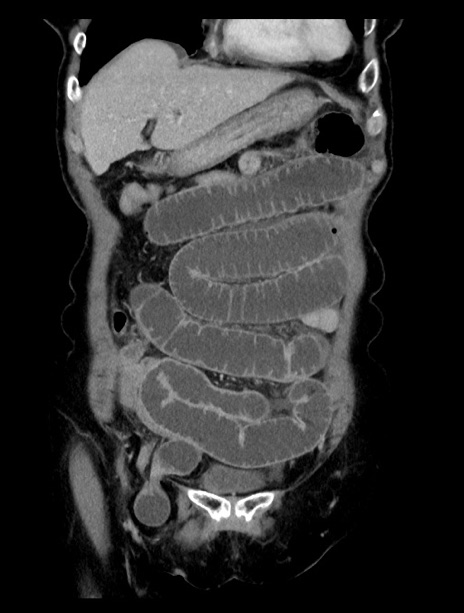

症例23(冠状断像)

【症例】70歳代女性

【主訴】下腹部痛・嘔吐

【現病歴】2日前より腹痛あり。昨日嘔吐あり。症状改善しないため来院。

【既往歴】胃GISTに対して胃部分切除後。

【身体所見】BT 37.1℃、BP 128/77mmHg、腹部:平坦・軟、下腹部に圧痛あり。

【データ】WBC 10200、CRP 0.31